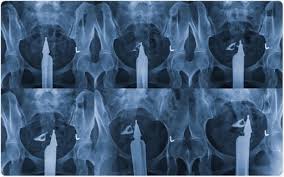

الرحم المقلوب الأسباب والأعراض والعلاج ويب طب